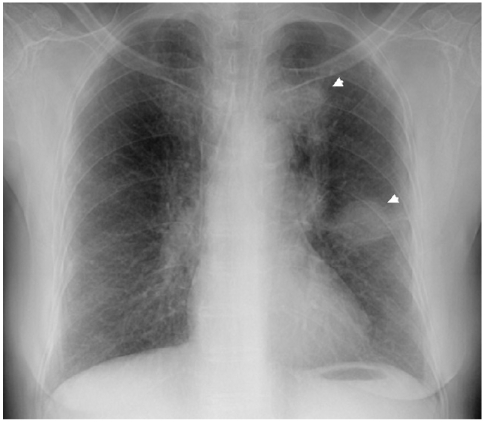

A 74-year-old woman came to our hospital for evaluation of her hemoptysis. Two distinct 3 cm-sized lung masses in the left upper lobe were found on the chest PA (Fig. 1). Squamous cell carcinoma was diagnosed by trans-thoracic needle biopsy of the lower mass. Although the other mass could have been a double primary carcinoma, further diagnostic tests were not done because the patient did not want them at that time. There was also enlargement of multiple mediastinal lymph nodes, suggesting that any benefit from radical treatment would not be great. After four cycles of chemotherapy with gemcitabine (1,000 mg/m2, days 1 and 8, every 3 weeks) and carboplatin (area under the curve: 6, day 1, every 3 weeks), the size of the two lung masses was decreased and so this was deemed a partial response. During the subsequent follow-up, the lung masses were again increased in size and she received second-line chemotherapy with two cycles of pemetrexed (500 mg/m2, day 1, every 3 weeks). After completion of chemotherapy with pemetrexed, the lower mass was markedly resolved while the upper mass did not respond (Fig. 2). Biopsy to the other mass was performed to determine whether it was a double primary carcinoma. However, the histology was almost same as the previously obtained specimen, and this made it difficult to differentiate the mass from metastasis (Fig. 3). Considering her age and performance, we decided not to administer further chemotherapy and so we recommended regular follow-up.

Figure 1

The initial chest radiograph shows two round lung masses in the left upper lobe.